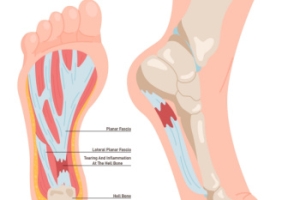

Key Insights Into Foot Pain From Plantar Fasciitis

Plantar fasciitis, a common foot ailment, affects millions of individuals worldwide, causing discomfort and hindering mobility. This condition occurs when the plantar fascia, a thick band of tissue connecting the heel bone to the toes, becomes inflamed or strained. It is characterized by sharp pain at the bottom of the foot, particularly near the heel, especially noticeable during the first steps in the morning or after prolonged periods of rest. While the exact cause remains elusive, factors such as overuse, improper footwear, high-impact activities, and tight calf muscles contribute to its onset. Plantar fasciitis is prevalent among athletes, runners, and individuals who spend extended periods on their feet. Fortunately, conservative treatments like rest, stretching exercises, and orthotic inserts, can alleviate symptoms and promote healing in many cases. However, persistent cases may require medical intervention, including corticosteroid injections or surgical procedures. If you have heel pain, it is suggested that you confer with a podiatrist who can accurately diagnose and treat plantar fasciitis.

What Is Plantar Fasciitis?

Plantar fasciitis is the inflammation of the thick band of tissue that runs along the bottom of your foot, known as the plantar fascia, and causes mild to severe heel pain.

What Causes Plantar Fasciitis?

- Excessive running

- Non-supportive shoes

- Overpronation

- Repeated stretching and tearing of the plantar fascia

The plantar fascia is a connective tissue in the heel that stretches across the bottom length of your foot. Plantar fasciitis occurs when the connective tissue becomes inflamed, causing heel pain and discomfort during physical activity. Although the condition is completely treatable, traditional methods can take up to a year to start becoming effective.

Plantar fasciitis is caused by a number of everyday activities, so understanding the condition is important for managing and treating it. One of the most common causes of plantar fasciitis is excessive running, especially with improper fitting or non-supportive shoes. Too much exercise can lead to the plantar fascia being overworked and overstretched, which can cause tears in the tissue. Along with improper fitting shoes, pronation, the rolling of the feet inward, is a common cause of plantar fasciitis. If not treated properly, the plantar fascia becomes overstretched and starts to tear, causing inflammation.

No matter what the case may be, consulting your podiatrist is the first and best step to recovery. Even the slightest amount of heel pain could be the first stage of plantar fasciitis. Untreated symptoms can lead to the tearing and overstretching of tissue. Because the tearing of tissue can be compounded if it remains ignored, it can evolve into a severe case. The solution is early detection and early treatment. Talk to your podiatrist about the possibilities of plantar fasciitis if you’re experiencing heel pain.